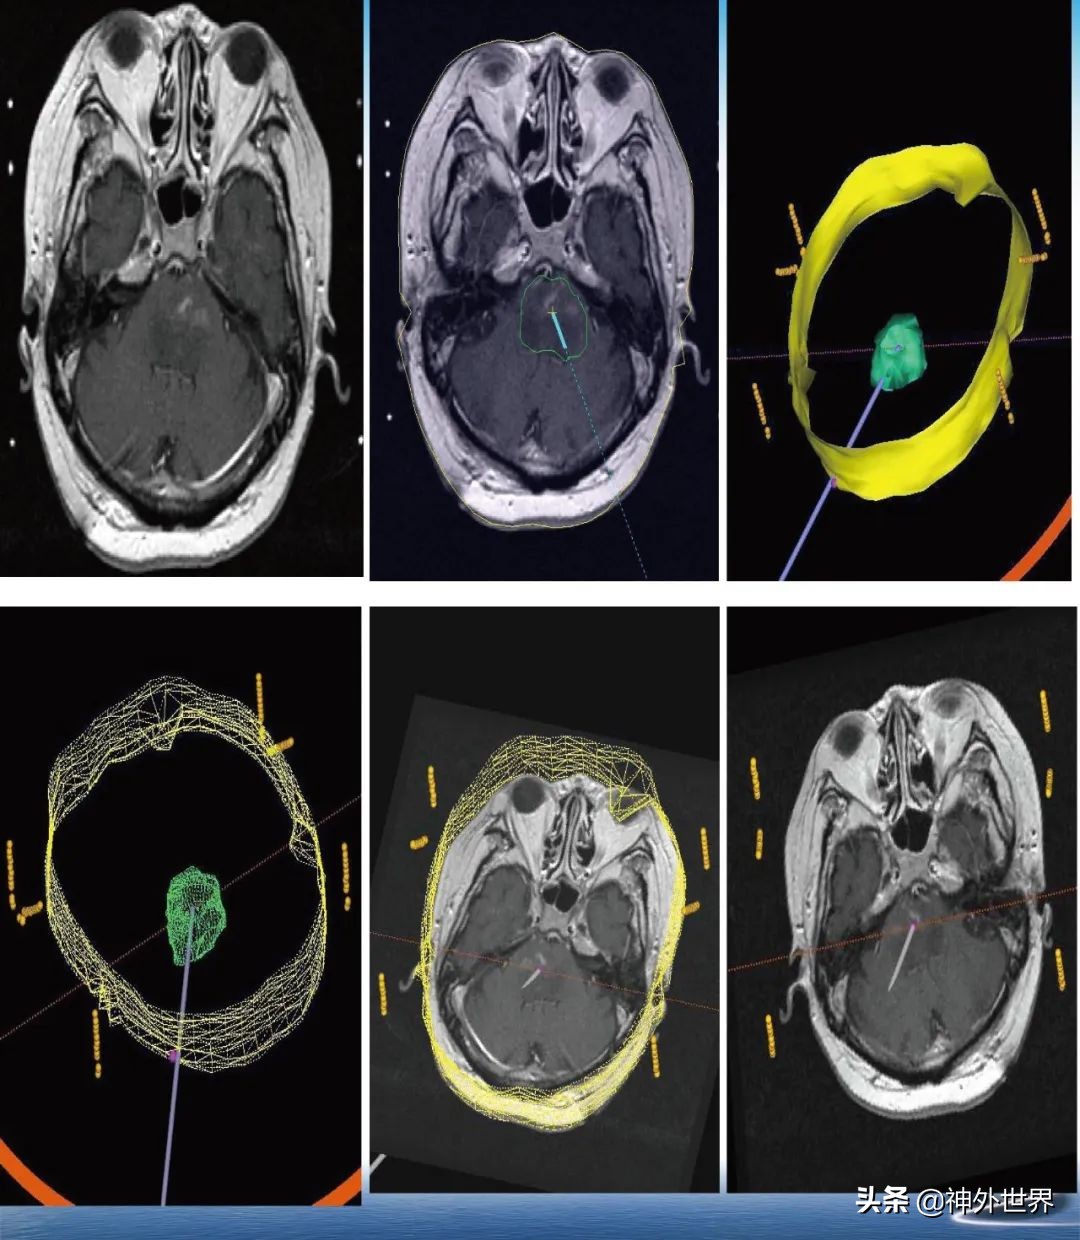

专业方向:颅内肿瘤的显微外科手术切除,颅咽管瘤综合治疗具有特色;在立体定向脑内病灶活检、立体定向清除脑干血肿、立体定向间质内放疗、机器人辅助神经外科手术方面具有专长。